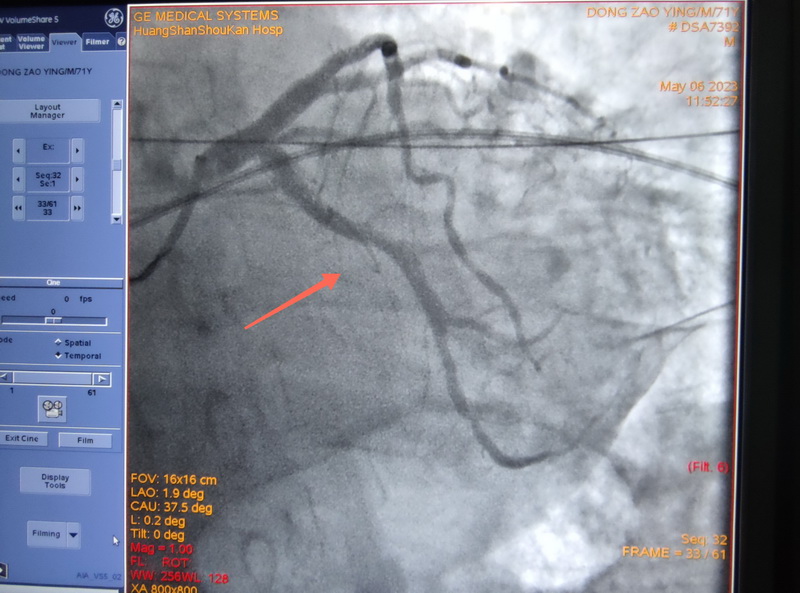

心内科主任吴捷华带领团队给董爷爷实施冠脉造影,显示回旋支完全闭塞伴血栓影,确定了回旋支是罪犯血管。医生们立即给董爷爷行冠脉内血栓抽吸和冠脉内溶栓,术中抽吸出几个较大的暗红色血栓。

抽吸和溶栓后,闭塞的回旋支恢复了正常血流。但术中未见回旋支明显狭窄,考虑是血栓栓塞引起的回旋支闭塞。那么血栓是哪里来的呢?